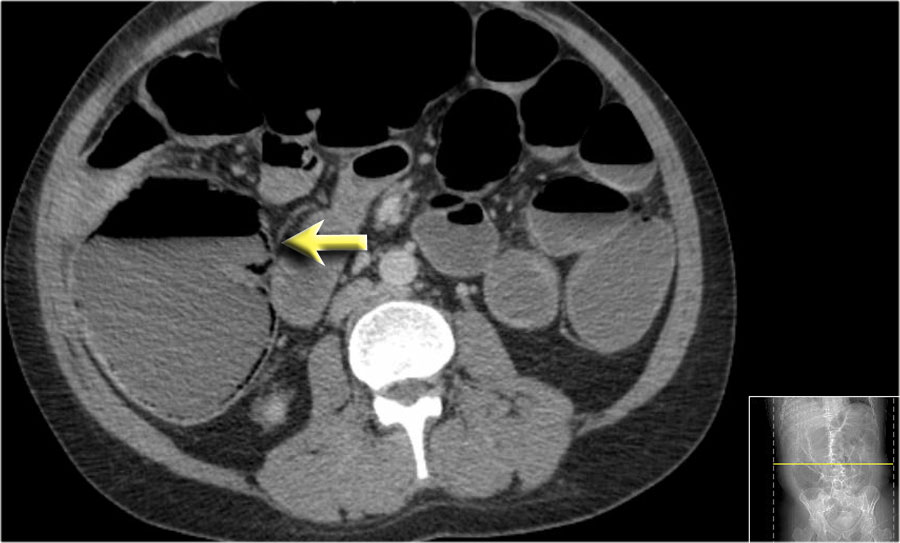

Các hình ảnh này thuộc về bệnh nhân bị tắc ruột non dạng quai kín.

Lưu ý nhóm các quai ruột non có thành dày ở vùng bụng trên phải (mũi tên vàng).

Phù nề mạc treo ruột (mũi tên đỏ) cho thấy tình trạng tăng áp lực tĩnh mạch do thắt nghẹt.

Giãn mạch máu

Tăng áp lực tĩnh mạch trong thắt nghẹt cũng dẫn đến giãn tĩnh mạch (mũi tên vàng).

Bệnh nhân này cũng có tắc ruột dạng quai kín với kiểu ngấm thuốc xám của các quai ruột bị thắt nghẹt (mũi tên đỏ).

Lưu ý sự ngấm thuốc bình thường của ruột non ở phía trên vị trí tắc nghẽn (mũi tên xanh lá).